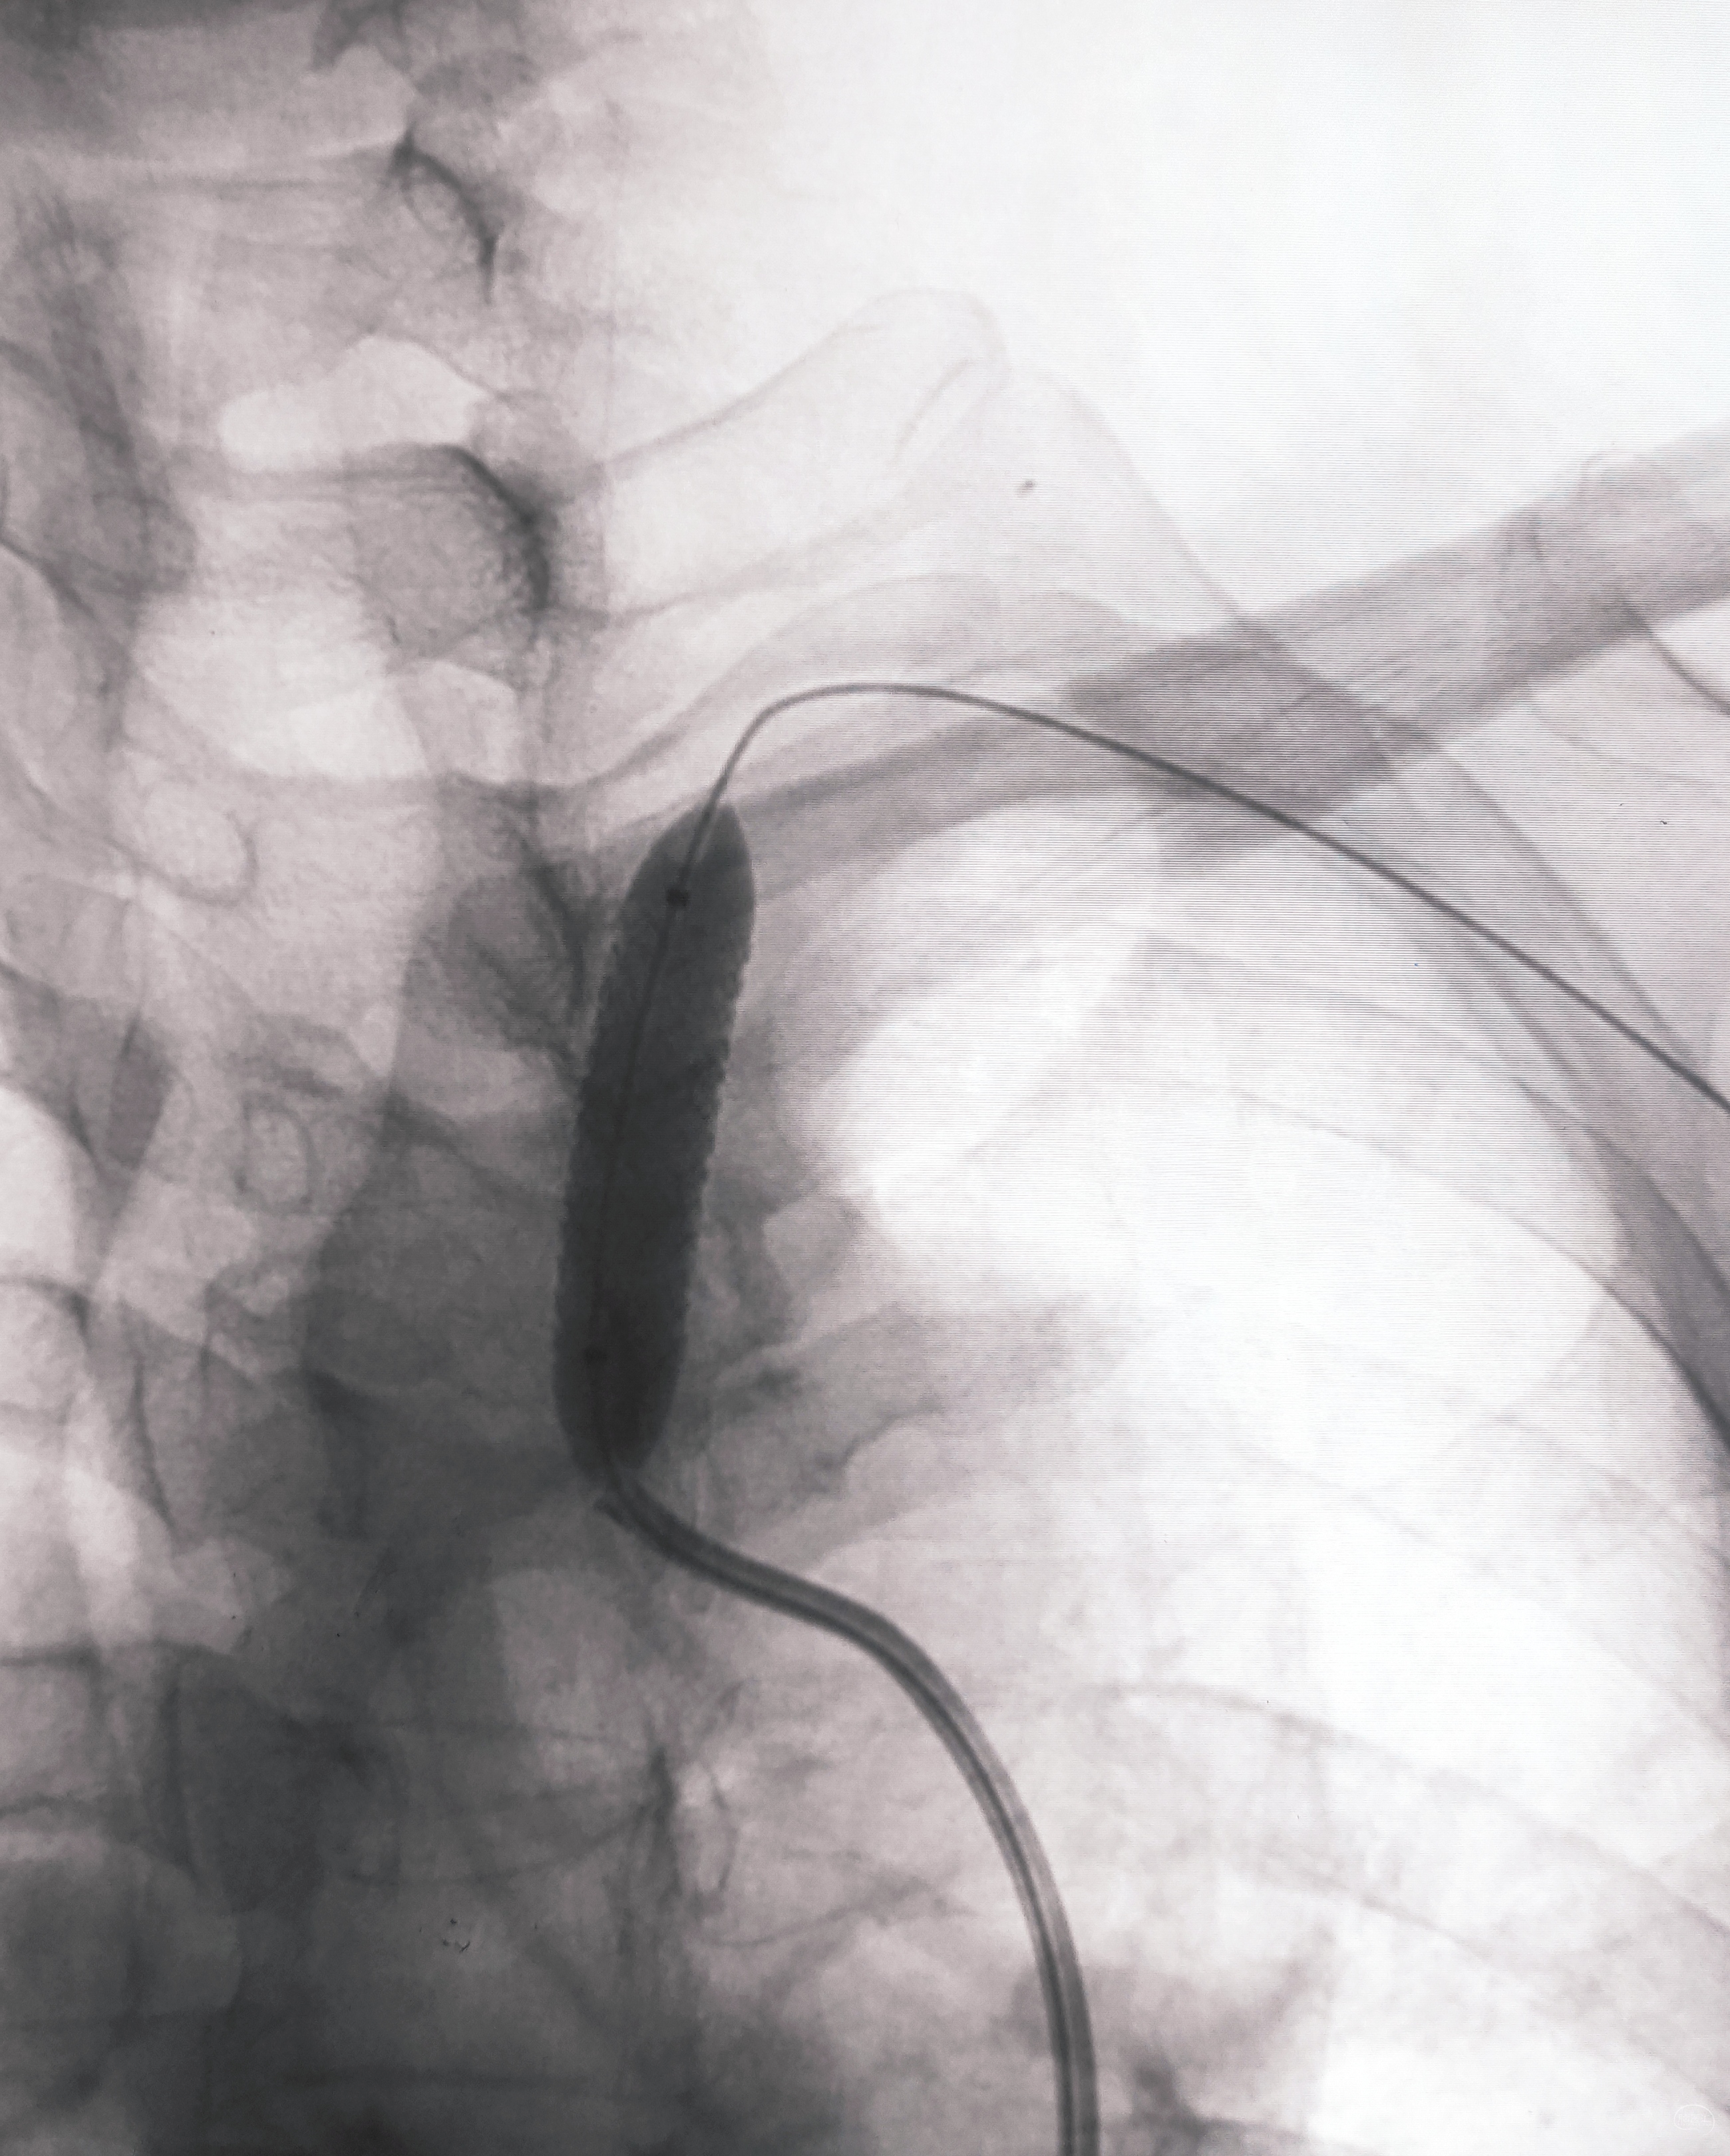

看图说话,没啥聊的。球囊不浪费,Sino3×20球囊预扩V4狭窄

EP4.5×22支架置入

导引导管保持原位,导管内安全输送Herculink5×20,通过椎开口狭窄并走远,再回撤导引导管至锁骨下动脉

球扩支架顺利释放